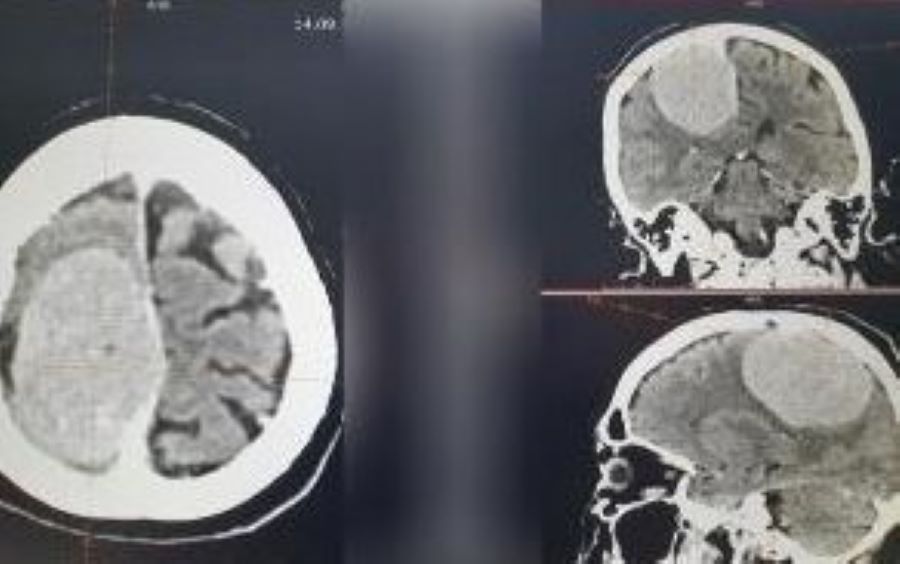

Орловские врачи успешно удалили огромную опухоль в головном мозге

Новый медицинский успех – в Орловской областной клинической больнице благополучно завершилась сложная операция по удалению опухоли в головном мозге. Огромное новообразование, размером почти с треть головы, отравляло жизнь 74-летней пациентки. Пенсионерка поступила в нейрохирургическое отделение с парасагиттальной менингиомой в правой теменной области. Симптоматика данного заболевания – головная боль, нарушение зрения, потеря памяти, судороги вплоть до эпилепсии.

– Операция проводилась по экстренным показаниям. Была выполнена костно-пластическая трепанация черепа с последующим микрохирургическим удалением опухоли головного мозга, – сообщается на портале области. Операцию проводило пять человек. Всё завершилось благополучно. Пациентку уже выписали из больницы с положительной динамикой. Впереди долгий процесс реабилитации.